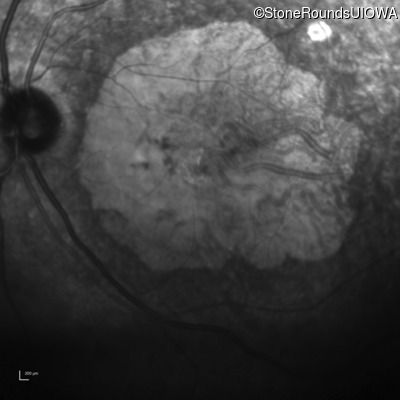

AR Stargardt Disease (IIA)

AR Stargardt Disease

ABCA4

Gly607Arg GGG>AGG

IVS30+1321 A>G

AR

Disease:

Gene:

Allele 1:

Allele 2:

Inheritance: